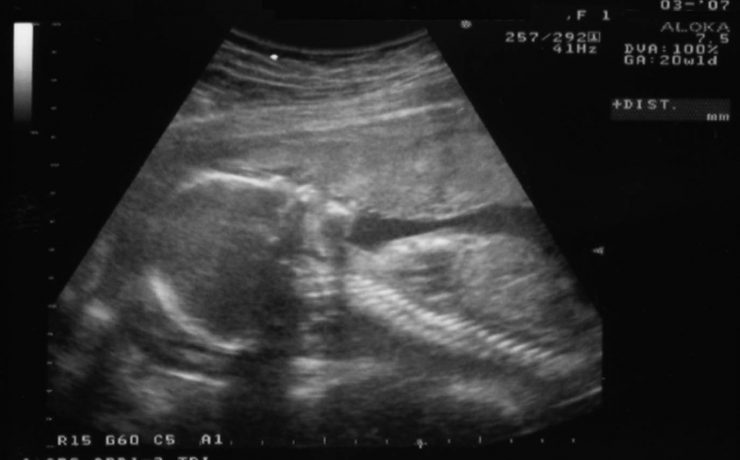

La ecografía del bazo.

La ecografía del bazo La ecografía del bazo es una parte fundamental del examen ecográfico completo, en el cual se evalúa el tamaño, forma, ubicación y parénquima del bazo, siendo necesario examinar y documentar estos aspectos detalladamente. Una de las principales ventajas de la ecografía es su amplia disponibilidad, bajo